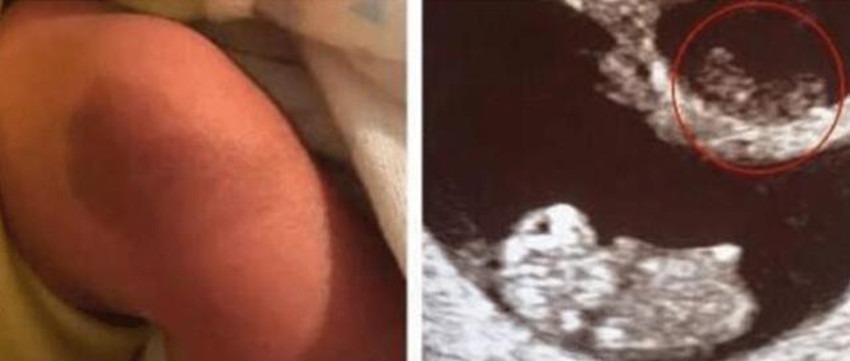

虽然说胎记是很常见的东西,但是这位小男孩的胎记,可能跟一般的胎记不太一样了。因为小男孩的胎记,其实就是双胞胎姐姐“幻化”而成的,其实当年这位妈妈在照B超的时候,发现自己怀的是双胞胎,本来是一件值得开心的事情,但是之后的产检过程中结果却并不乐观,因为医生告诉这位妈妈,只能听到了一个心跳,也就是说其中一个胚胎发育并不是很好,让妈妈做好心理准备,之后在怀孕13周的时候,医生通过B超检查,发现这个时候宝妈的腹中只剩下一个胎儿了,而另外一个胎儿,就被这个胎儿给“吸收”掉了。

对于这样的事情,这位妈妈也是有些难以接受,但是最后生下孩子的时候,发现孩子的腿上有一个特殊的胎记,这块胎记的形状跟那个被吸收掉的宝宝的B超影像非常相似,所以妈妈觉得,这是姐姐幻化成的胎记,也就是说姐姐从来就没有离开过,一直在自己的身边,网友纷纷表示,这就是最美的胎记。